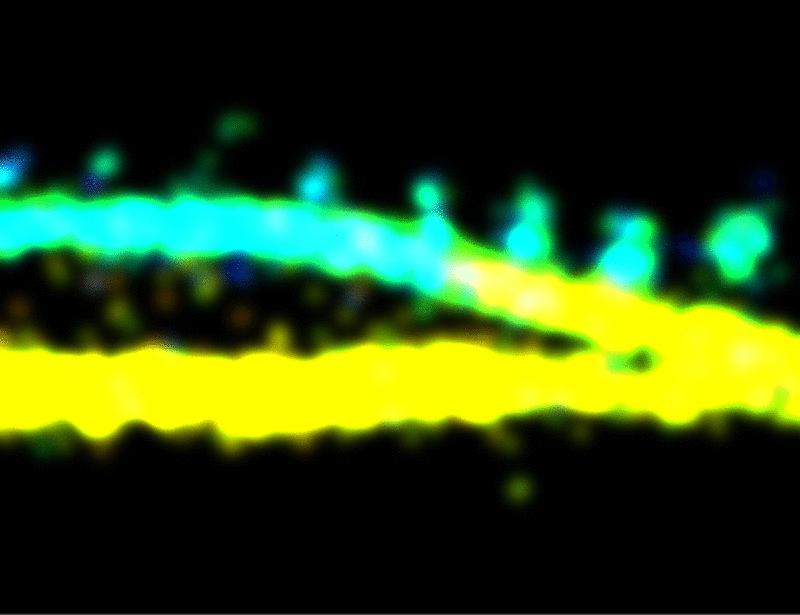

Actin depolymerization promotes axon regeneration by restoring axonal mitochondrial transport in mouse models of optic neuropathy | Science Translational Medicine

Actin depolymerization promotes axon regeneration and neuroprotection by enhancing axonal mitochondrial transport.